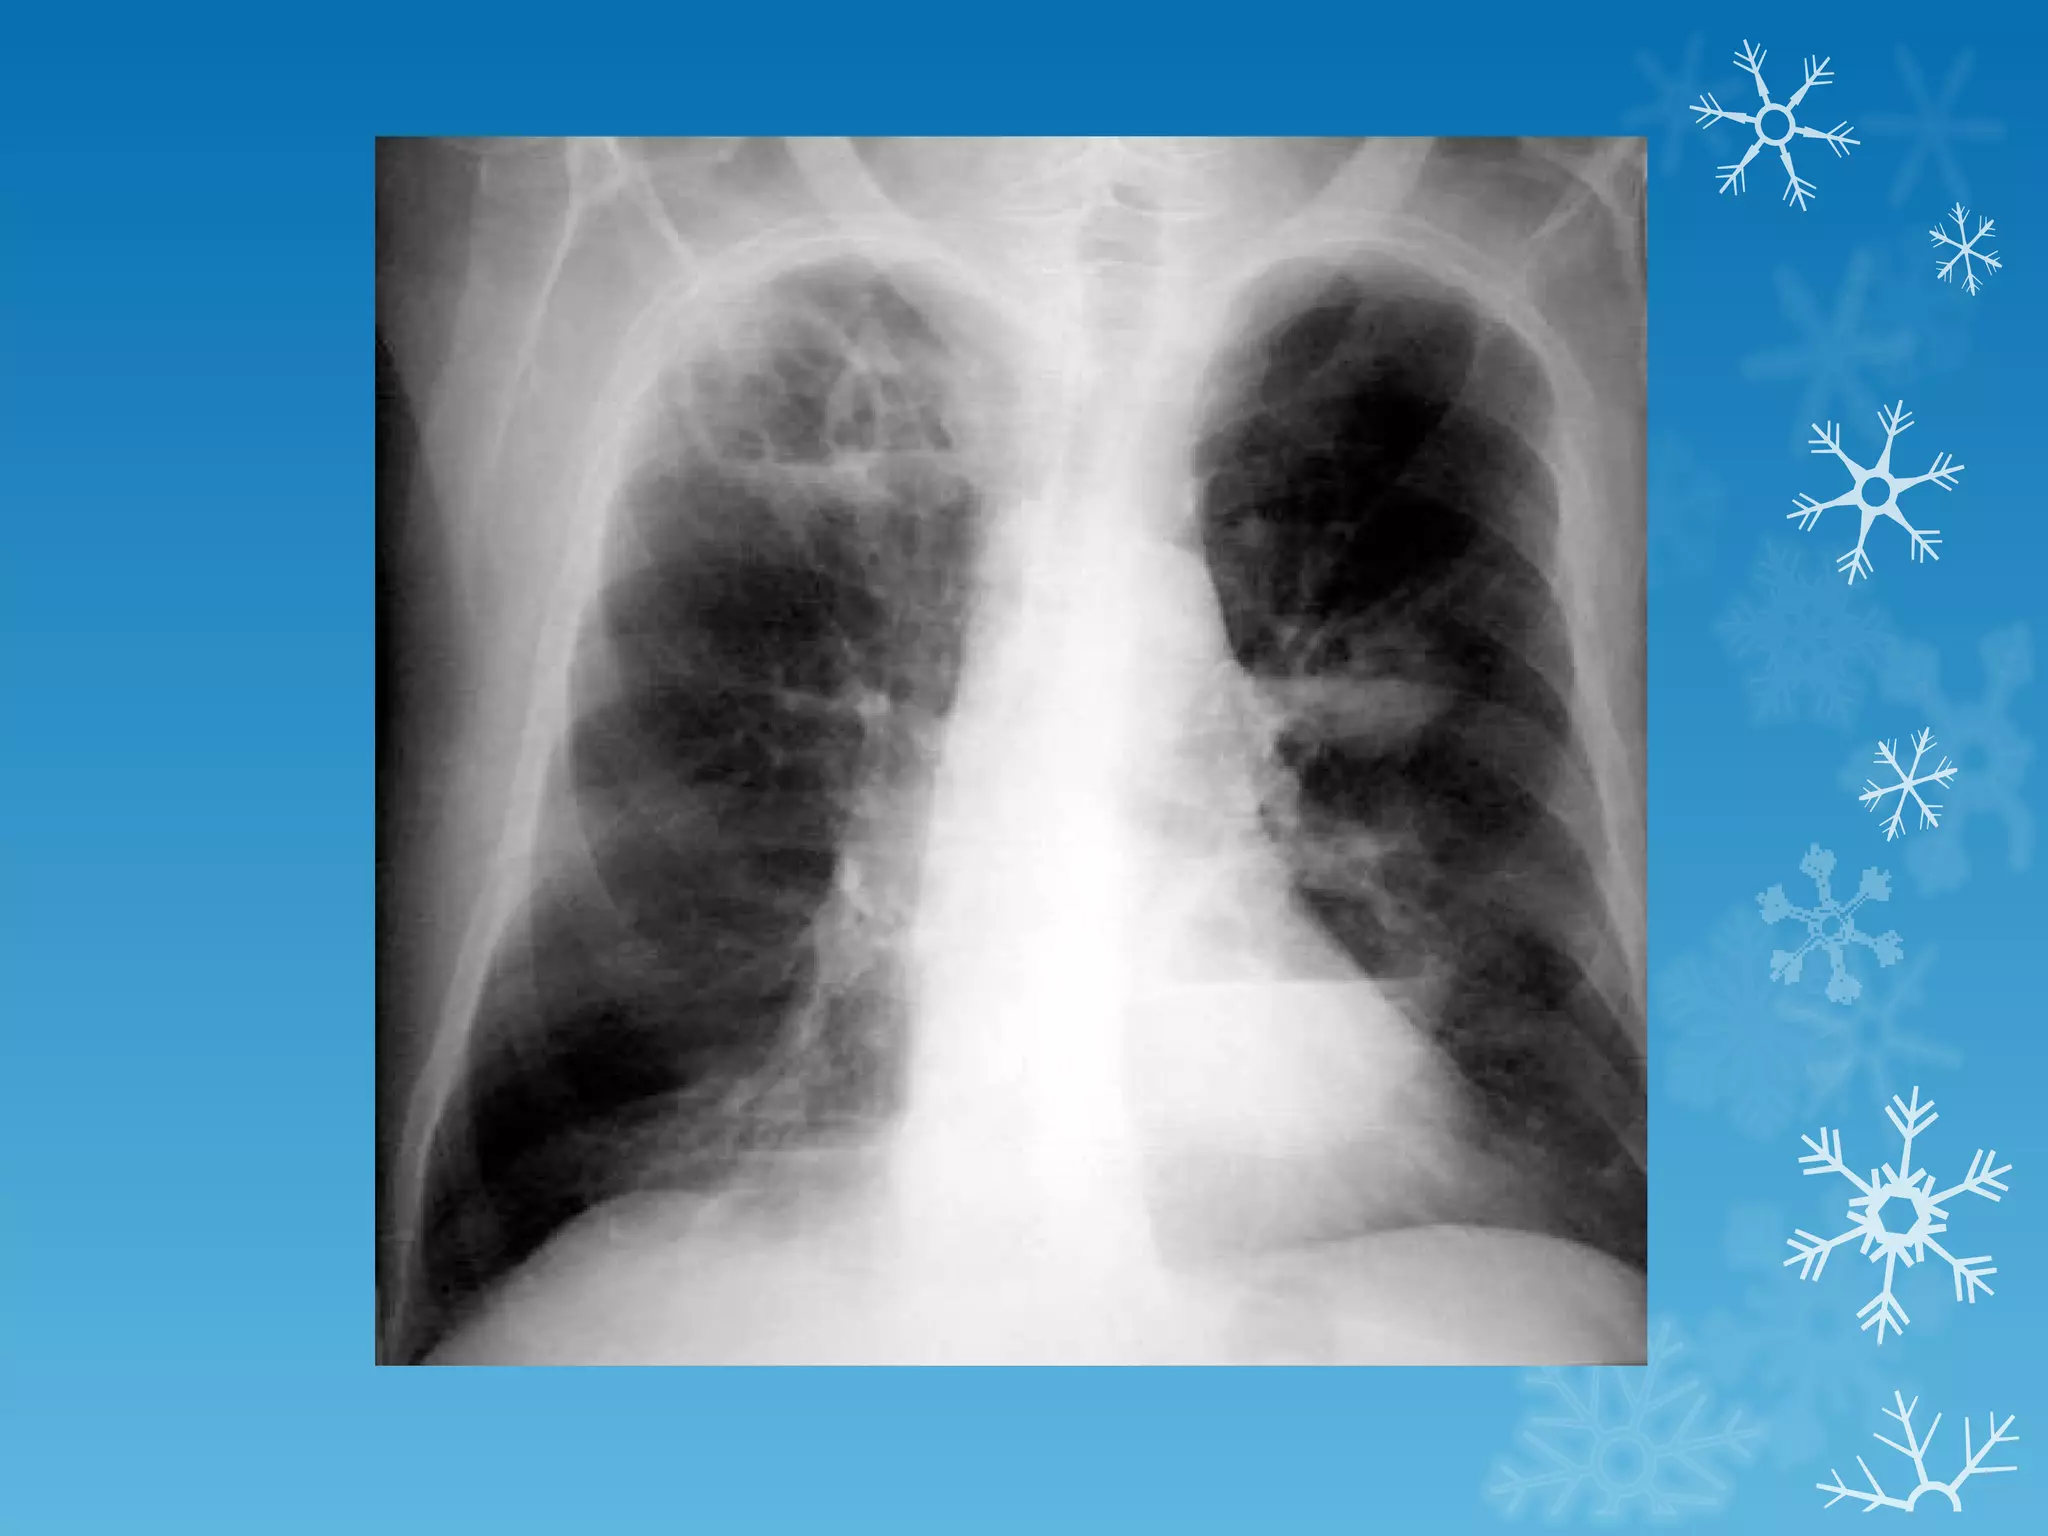

This document discusses chest x-ray interpretation and provides guidance on evaluating x-rays. It explains that tissue density determines how an x-ray beam penetrates, with denser tissues appearing whiter and less dense tissues appearing blacker. It also outlines different chest x-ray views and factors to consider like patient orientation, age, gender, and rotation. Abnormalities are described as appearing too white, too black, too large, or in the wrong place. The document stresses a systematic approach of identifying, localizing, describing lesions, and providing differential diagnoses.